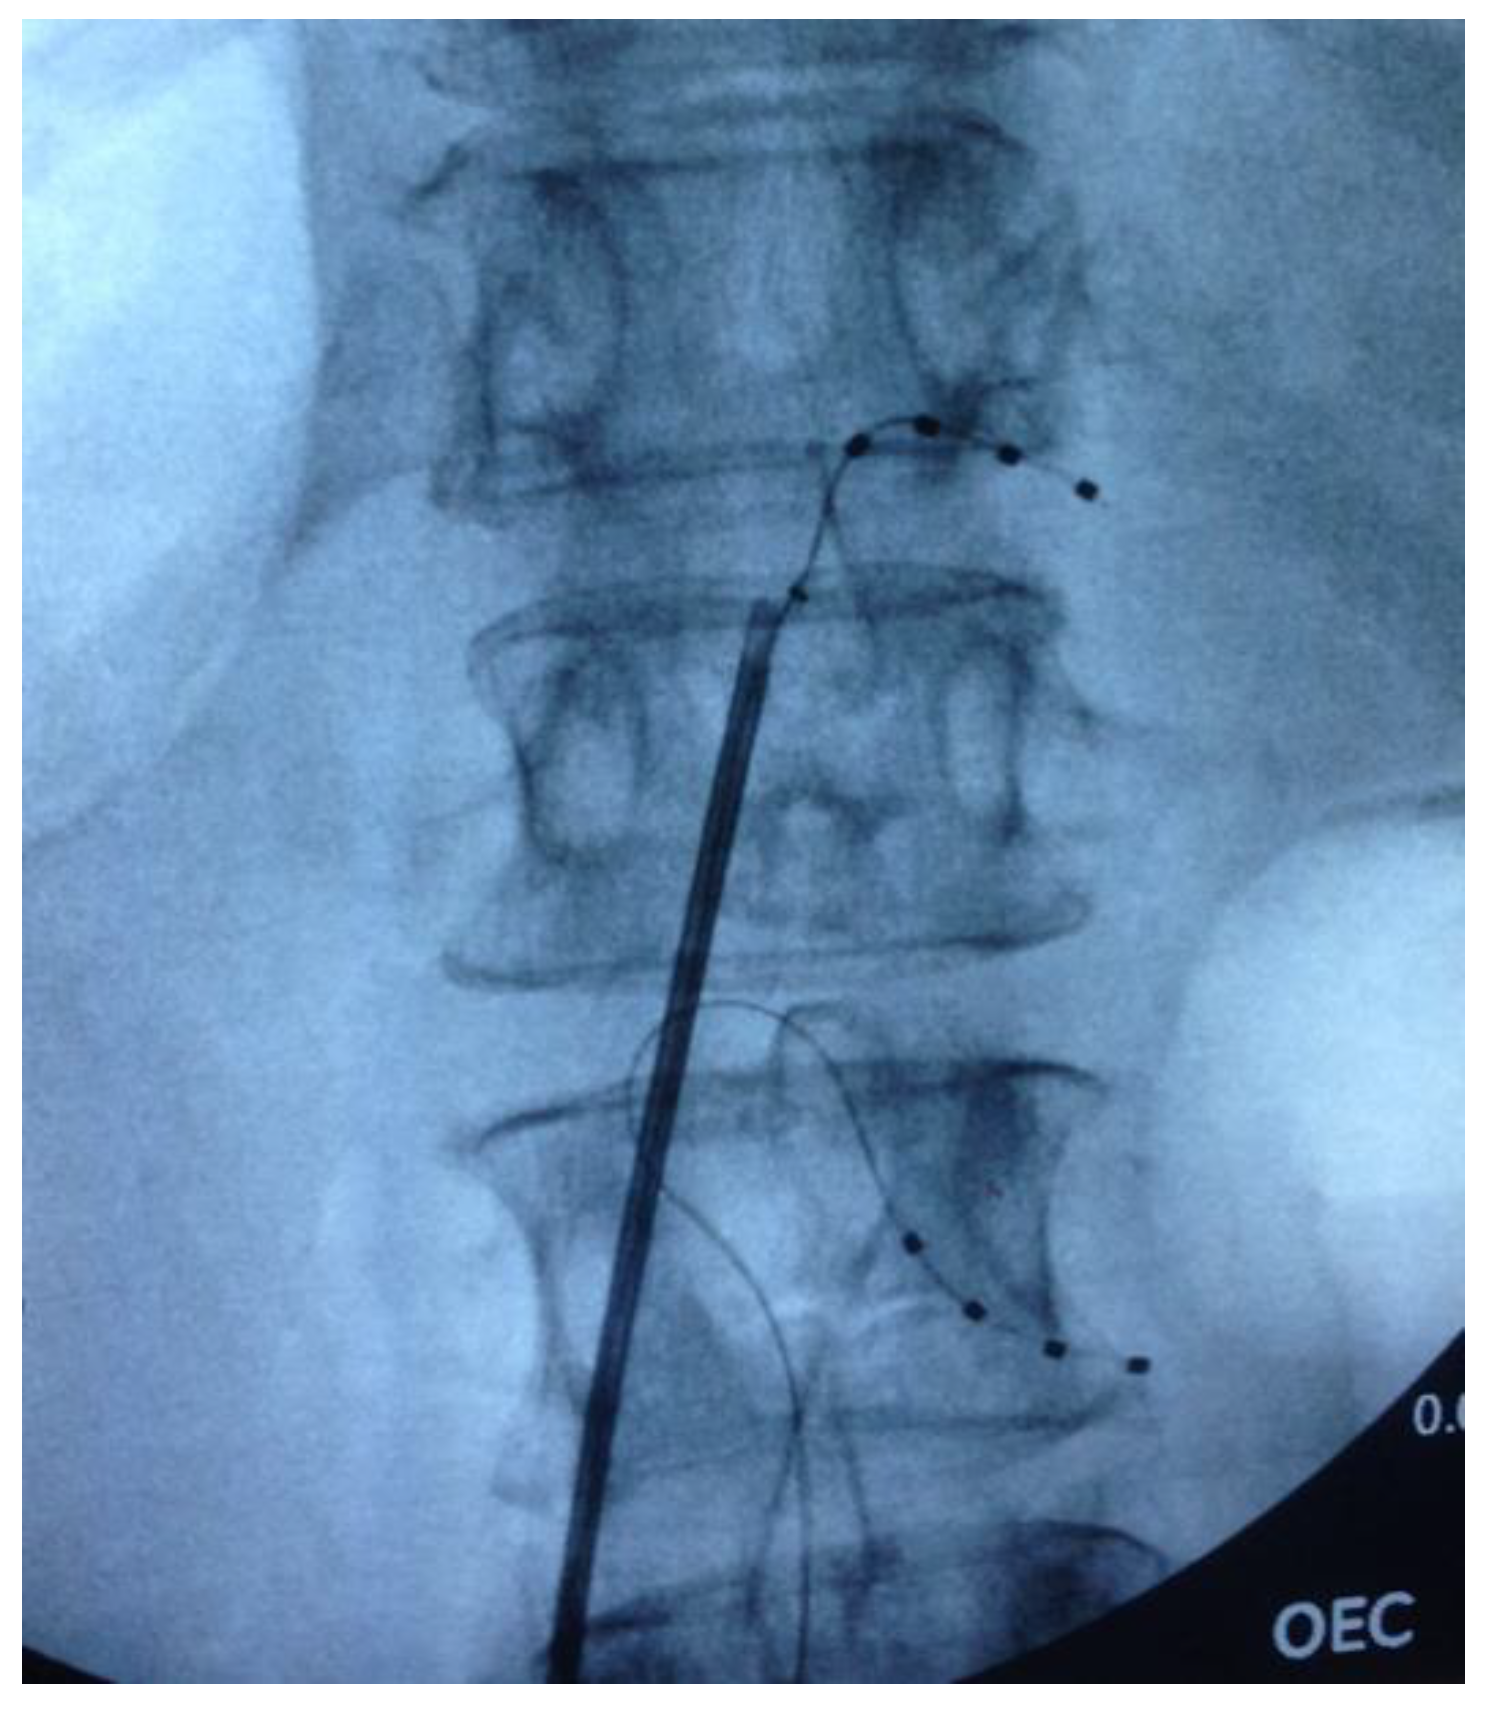

2.2. Surgical Procedure

| Patient | Age | Gender | Diagnosis | Electrode Location | Stimulation Parameters (Frequency (Hz)/Amplitude (mA)/Pulse Width (μs)) | |

|---|---|---|---|---|---|---|

| 1 | 49 | Female | Postherpetic neuralgia | Right L5 | 20/1.6/400 | |

| 2 | 53 | Female | Meralgia paresthetica | Right L2 | 20/0.6/300 | |

| 3 | 29 | Male | Post-traumatic compressive neuropathy | Left L2 | 20/0.7/250 | |

| 4 | 78 | Male | Diabetic neuropathy | Bilateral L5 | Right - 20/1.025/450 Left - 20/0.775/480 | |

| 5 | 46 | Male | CRPS | Right L3 | 20/0.7/410 | |

| 6 | 52 | Male | Post-operative nerve entrapment | Left L1 | 28/1.3/250 | |

| 7 | 58 | Female | CRPS | Right L2/L3 | 20/2.1/250 | |

| 8 | 61 | Male | Post-operative mononeuropathy | Left L3 | 20/2.1/140 | |

| 9 | 47 | Male | CRPS | Left L4 | 20/6/350 | |

| 10 | 55 | Male | Nerve entrapment | Right C7/C8 | 20/0.425/300 | |

| 11 | 29 | Male | Post-operative radiculopathy | Bilateral L5 | Right - 20/2.25/700, Left - 20/650/800 | |

| 12 | 52 | Female | CRPS | Right L5 | 30/0.7/500 | |

| 13 | 77 | Female | Postherpetic neuralgia | Right T1 | 30/0.4/300 | |

| 14 | 22 | Female | Dystonic pain | Right L2/L3 | 20/2.4/300 | |

| 15 | 52 | Male | Post-operative mononeuropathy | Right L1 | 30/0.525/400 | |

| 16 | 54 | Male | Post-operative radiculopathy | Right L3/L4 | 20/0.475/360 |